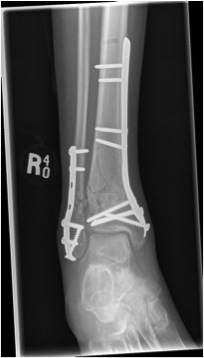

B. Distal Tibial ORIF with plate

Indications

- too distal to nail

- very comminuted / unstable

- intra-articular extension

Technique

1. Consider fixing the fibula

- will aid reduction / avoid malunion

- help control very unstable fractures

2. Anatomically contoured plates

- options of medial plate v anterolateral plate

- medial plate for varus deformity

- anterolateral plate for valgus deformity